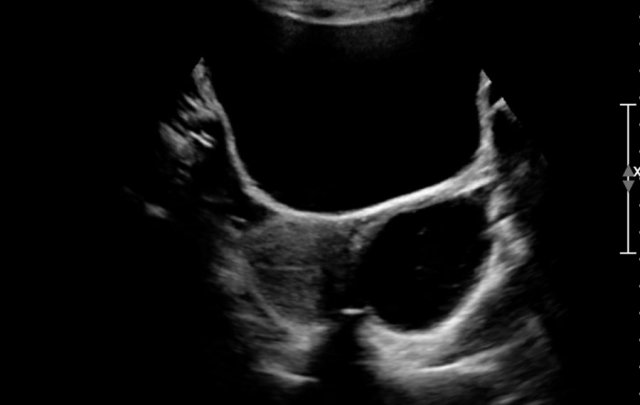

Antenatally a duplex system of the left kidney was diagnosed with hydronephrosis. A postnatal ultrasound demonstrates a large cyst in the upper pole of the left kidney and some smaller cysts (not shown).

No normal parenchyma was visible.

On MCUG reflux in the lower pole system is seen, which is displaced caudally and rotated due to the upper pole mass.

This is probably a MCKD confined to the upper pole.

MCKD can affect one pole of a duplicated pelvicocalyceal system.